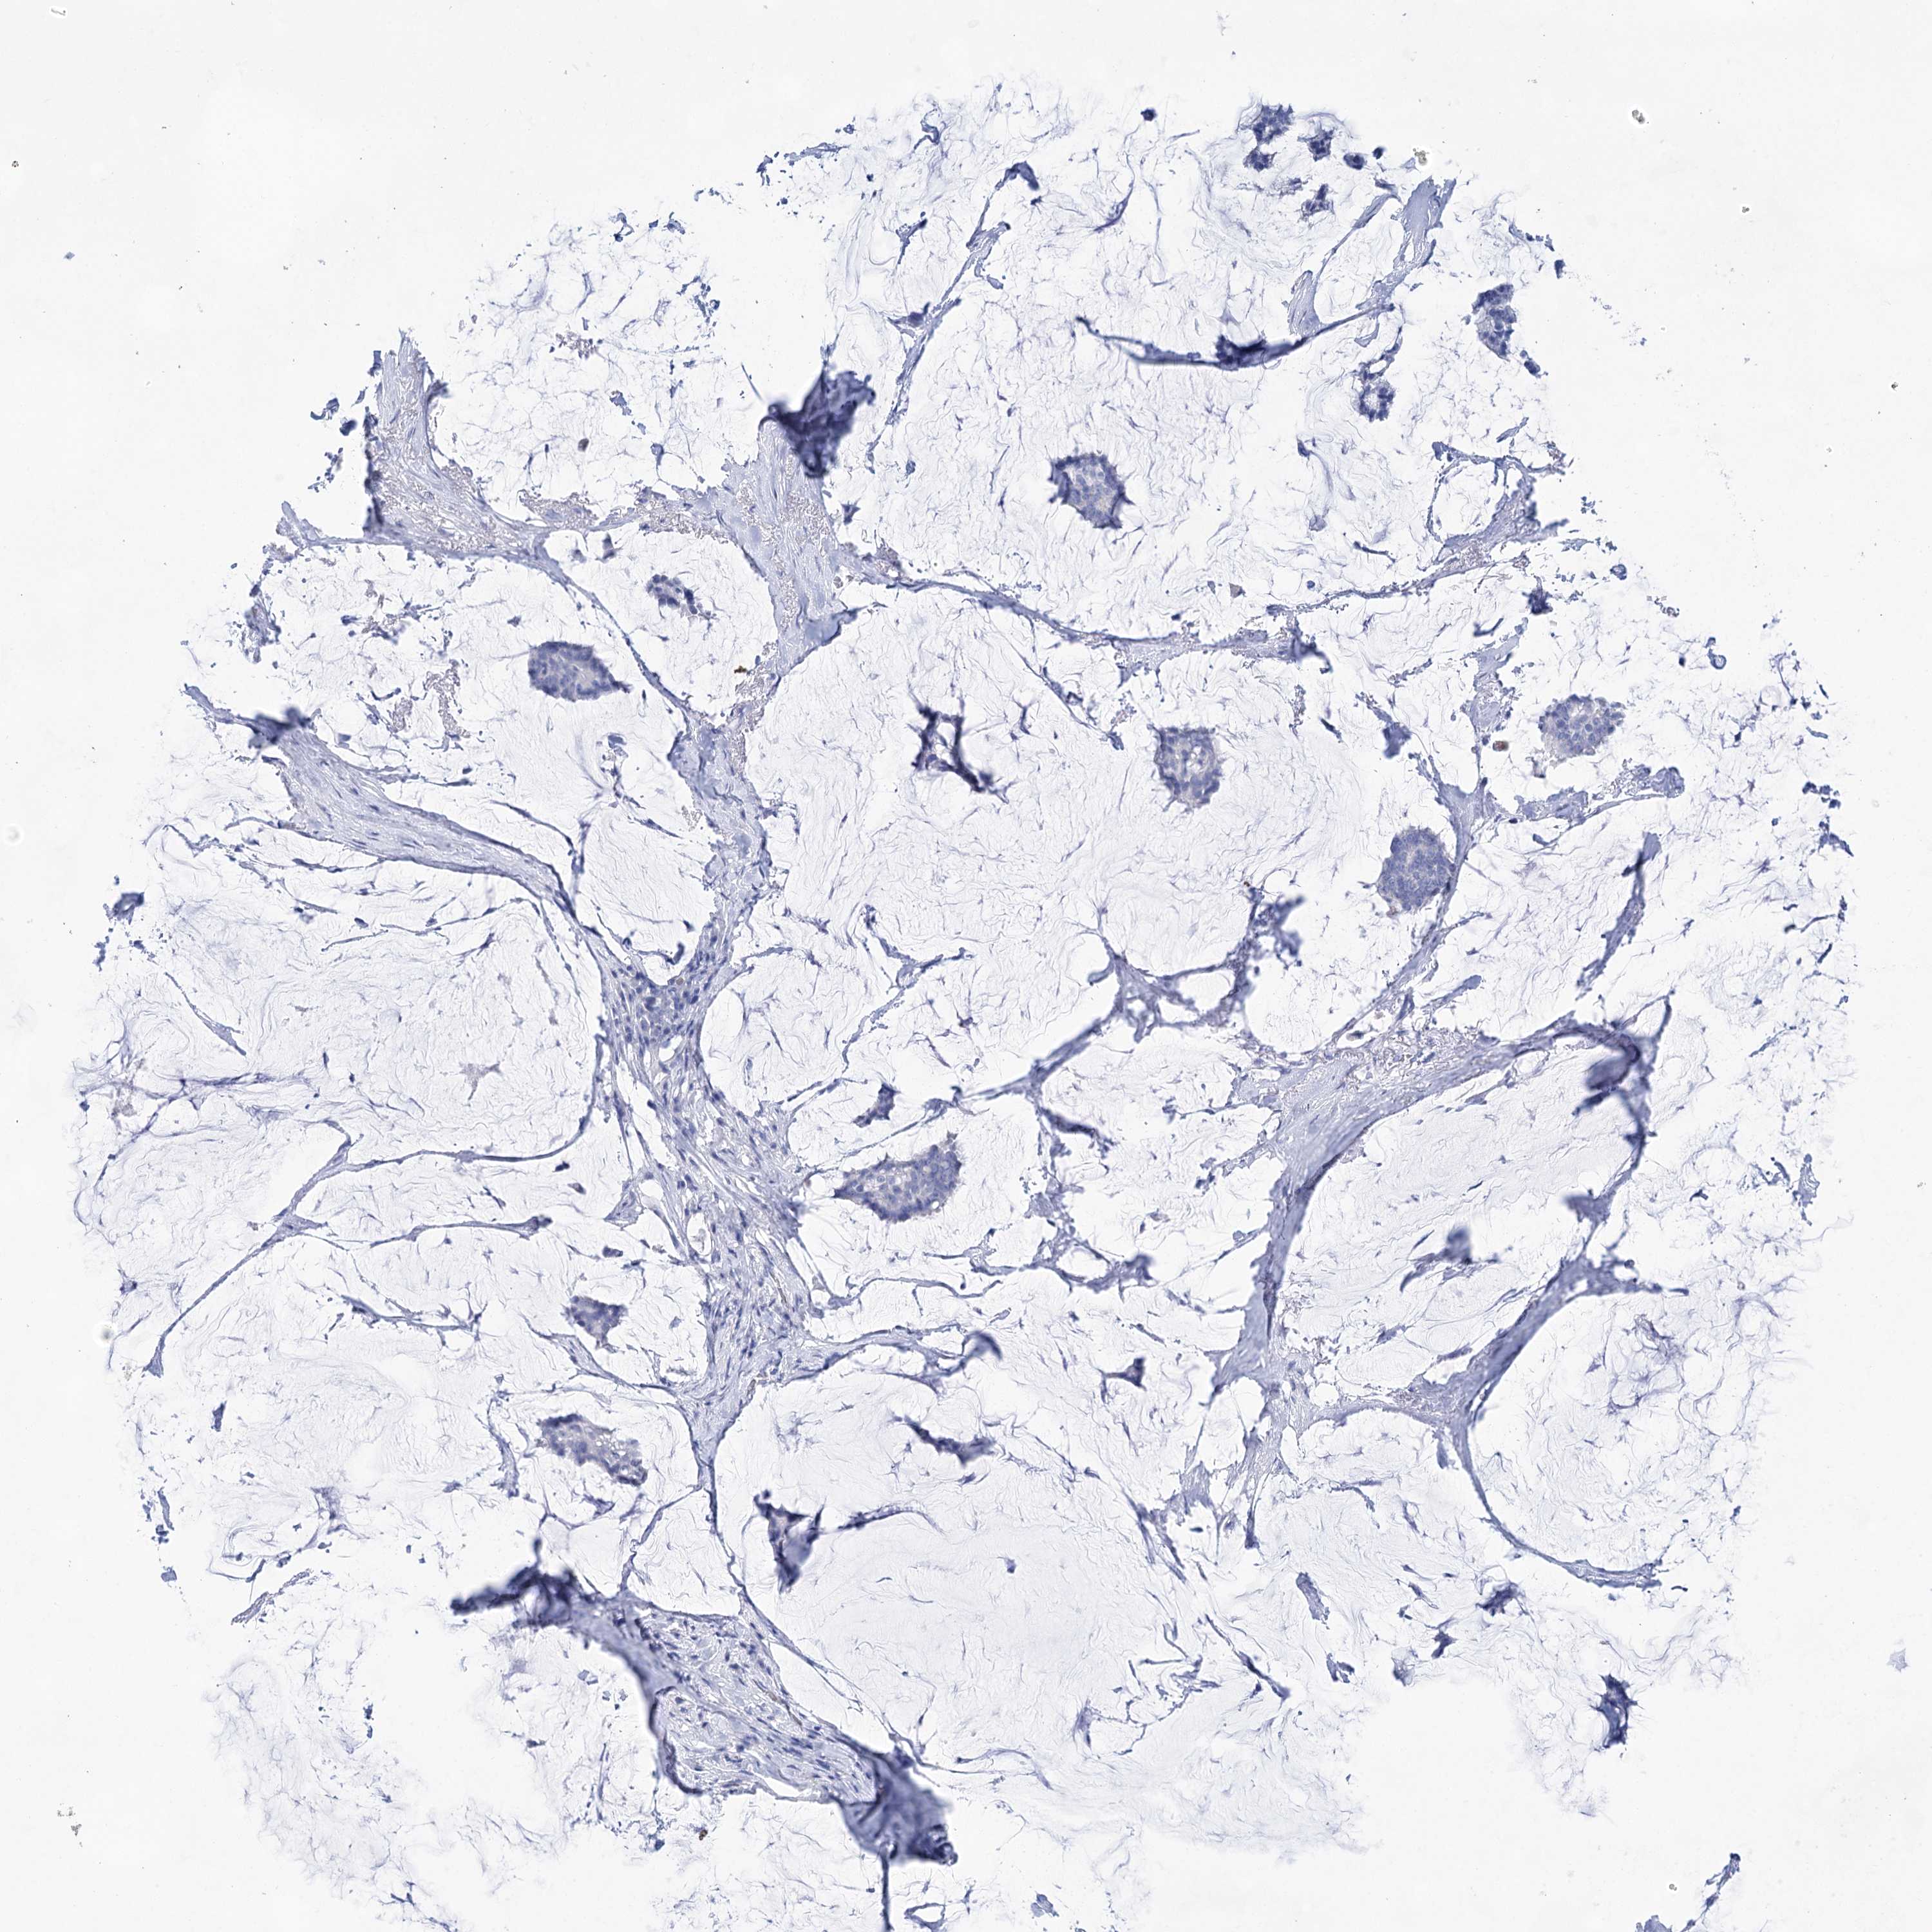

Breast cancer

Human cancer